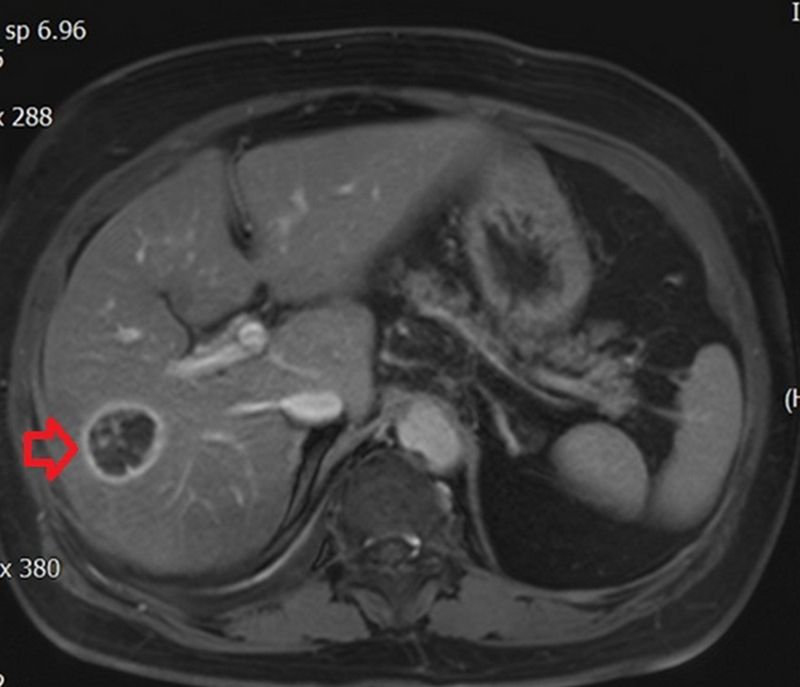

【記者盧世光/綜合報導】年近八旬的許奶奶患有慢性肺病、心臟衰竭、糖尿病、高血壓等多種慢性疾病,長期於台北慈濟醫院胸腔內科及感染科追蹤看診。半年前回診發現肝指數過高,感染科醫師遂安排腹部超音波檢查,結果發現脂肪肝及肝臟一顆約三公分大腫瘤,故轉診至胃腸肝膽科陳泓達醫師門診進一步檢查。後續經由電腦斷層、磁振造影檢查,診斷為肝癌,陳泓達醫師考量許奶奶肝功能及身體狀況執行「腫瘤射頻燒灼術」,術後三天,許奶奶平安出院。

肝癌的診斷除了觀察臨床表現外,還需藉由抽血檢查檢驗肝功能狀態,並利用腹部超音波、電腦斷層或核磁造影等相關檢查確認腫瘤型態、大小以及是否有轉移。在手術治療方面,除了傳統開腹手術、微創腹腔鏡或達文西手術外,尚有腫瘤射頻燒灼術的選擇,主要運用於腫瘤小於2至3公分的患者或心肺功能無法負荷麻醉或手術風險較高的病患;腫瘤大於3公分以上的患者是否適用則需醫師詳細評估。以許奶奶為例,慢性疾病較多、身體機能較差,經多團隊會議及家屬溝通後,射頻燒灼術治療是最妥適的選擇。首先以超音波定位確認病灶,再以電燒針穿刺至腫瘤中央,在腫瘤內產生高熱使癌細胞壞死,達到治療目的。陳泓達醫師提到:「射頻治療的治療時間約落在數十分鐘左右,對病人的影響較輕,在審慎評估後適用的病患族群預後效果與其他手術相當,是肝癌治療的另一種選擇。」